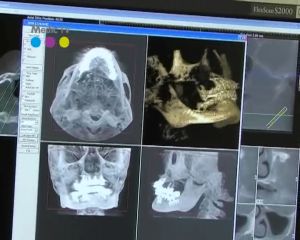

Digitální stomatologické CT i-CAT je nové, vyspělé zařízení zpřístupňující 3D technologii stomatologům, které mění pohled na diagnostiku a plánování léčby. Interpretace trojrozměrných anatomických struktur z dosud běžně používaných dvojrozměrných rentgenových snímků vyžaduje od ošetřujícího dostatečnou představivost, značnou zkušenost a někdy i štěstí. Navíc v sobě ukrývá nebezpečí nepřesné či špatné diagnózy a omezuje možnosti detailní lokalizace a proměření dentálních struktur.

Prostorový snímek vyhotovený novým CT zařízením hodnocení nálezu podstatně zjednodušuje. Díky přesnému 3D zobrazení je analýza jednoznačnější, rychlejší a méně závislá na zkušenosti ošetřujícího. A především umožňuje zcela přesné proměřování v prostorových souvislostech, což je důležité při přesném plánování co nejúčinnější léčby.

Další podstatný rozdíl mezi stomatologickým CT (Cone-beam-CT) a klasickým CT je mnohonásobně nižší dávka RTG záření, které na pacienta působí při vyšetření stomatologickou technologií. Je to způsobeno tím, že při Cone-beam-CT technice rentgenový paprsek nevytváří vějíř jako u klasického CT, nýbrž konický svazek paprsků. Objekt tak může být zobrazen při pouhém jednom oběhu. Svazek paprsků je zachycen na obdobný senzor jako u klasického CT přístroje. Pomocí vhodných algoritmů jsou jednotlivé vrstvy převedeny do prostorového obrazu.